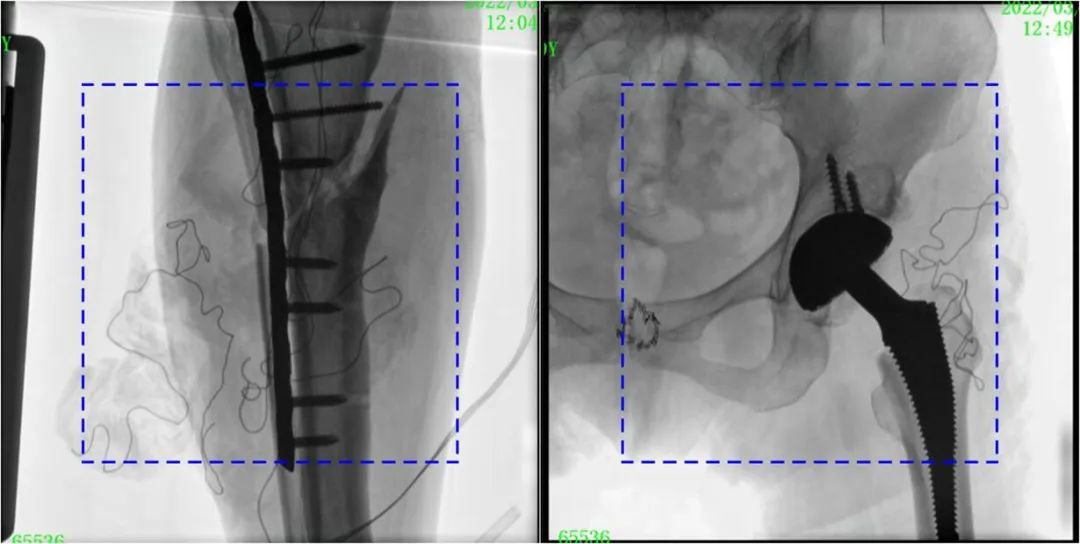

与传统的21CM×21CM成像尺寸相比,糖心vlog 大平板一体式C形臂具有30CM×30CM更大成像尺寸,能够一次成像5.5节椎体,呈现更全面的影像信息,即便是手术经验不丰富的年轻医生也能通过图像迅速判断椎体节段、定位手术部位,避免因为视野不足而造成的多次定位、反复曝光,提高效率的同时避免过量摄入辐射。

大平板一体式C形臂图像与传统图像对比(蓝色虚线内为传统21CM×21CM平板的成像区域)